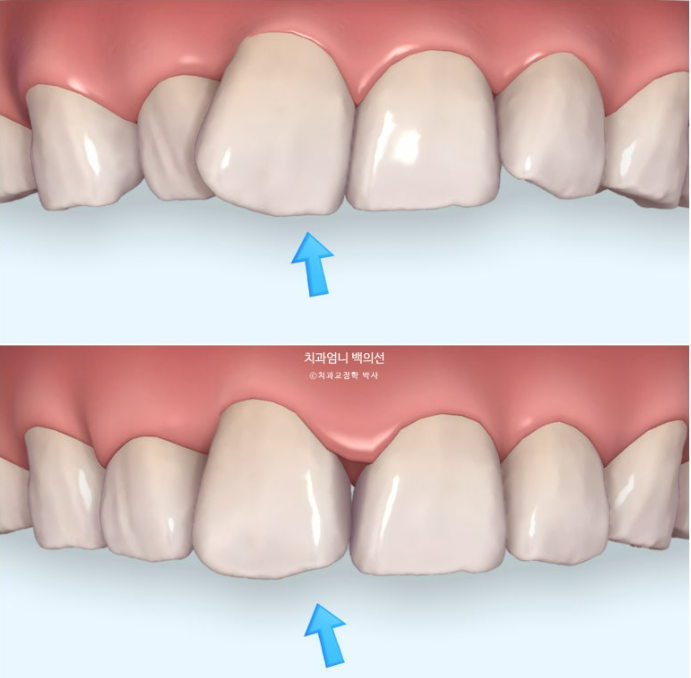

특히 이 경우 튀어나온 앞니가 사선으로 비스듬히 마모된 부분이 있어서 미리 사전에 눈으로 확인시켜드리기 위해서 시뮬레이션을 활용하고 있습니다.

그렇지 않으면 치아가 배열되면서 마모된 부분이 드러나며 교정 중 치아가 깨졌다 또는 기울어졌다 라고 오해하실 수 있기 때문입니다

위가 치료 전 아래가 치료 후 예상 시뮬레이션 입니다.

파란 화살표 부위의 비스듬히 마모된 부분이 교정 전에는 티가 안나다가 배열이 완료가 되면 비로소 티가 많이 나게 되는거죠.

이런 경우 마모된 부분을 레진으로 수복하기 보다는 티가 덜나게끔 끝단을 조금 편평하게 다듬으면 좋습니다.